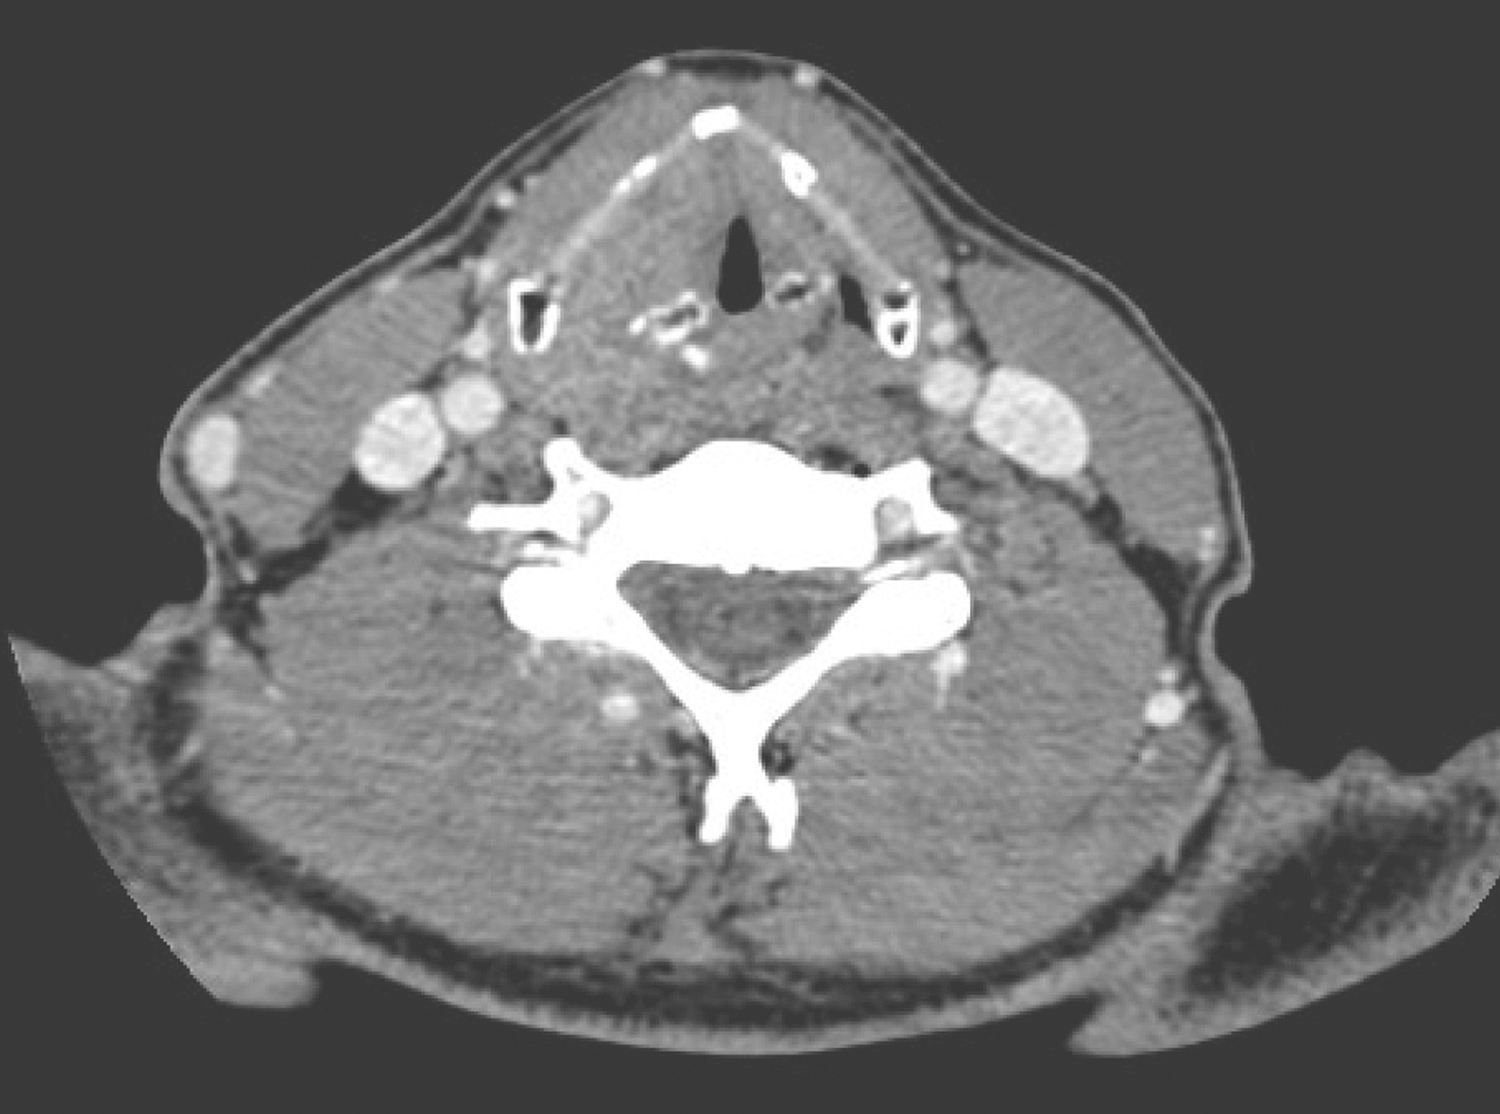

1小时条评论50岁男性,因咽部疼痛、不适感10个月,声音嘶哑半年,饮水呛咳伴呼吸憋闷1个月余住院治疗。如何进行综合治疗? 【病例简介】 患者男性,50岁。因咽部疼痛、不适感10个月,声音嘶哑半年,饮水呛咳伴呼吸憋闷1个月余住院治疗。患者10个月前即有咽部疼痛、不适...

1小时条评论51岁男性,半年前出现咽部不适感,近2个月来加重并声音嘶哑。曾以咽炎口服中成药治疗,效果不佳。如何诊治? [病例简介] 患者男性,51岁。因咽部不适感半年,加重并声音嘶哑2月余住院治疗。患者半年前即有咽部不适感,无明显疼痛,无吞咽阻挡感,未予在意。...

1小时条评论51岁男性,6个月前无明显诱因出现咽部异物感,1个月前出现咽部疼痛,呈钝痛,吞咽时加重。门诊行电子喉镜检查见左侧梨状窝粗糙新生物,如何诊治? 【病例简介】 患者男性,51岁。因咽部异物感6月余,咽痛1月余住院治疗。患者6个月前无明显诱因出现咽部异物感...

1小时条评论48岁男性,因左颈肿物伴咽痛3个月余,肿物生长明显伴呼吸困难2周气管切开后收入头颈放疗科。如何选择治疗方案? 【病例简介】 患者男性,48岁。因左颈肿物伴咽痛3个月余,肿物生长明显伴呼吸困难2周气管切开后于2011年8月31日收入头颈放疗科。3个月前患者无意中发...